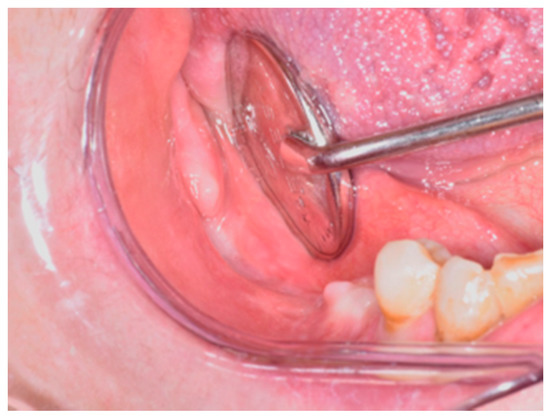

2. Materials and Methods

3. Results

4. Discussion